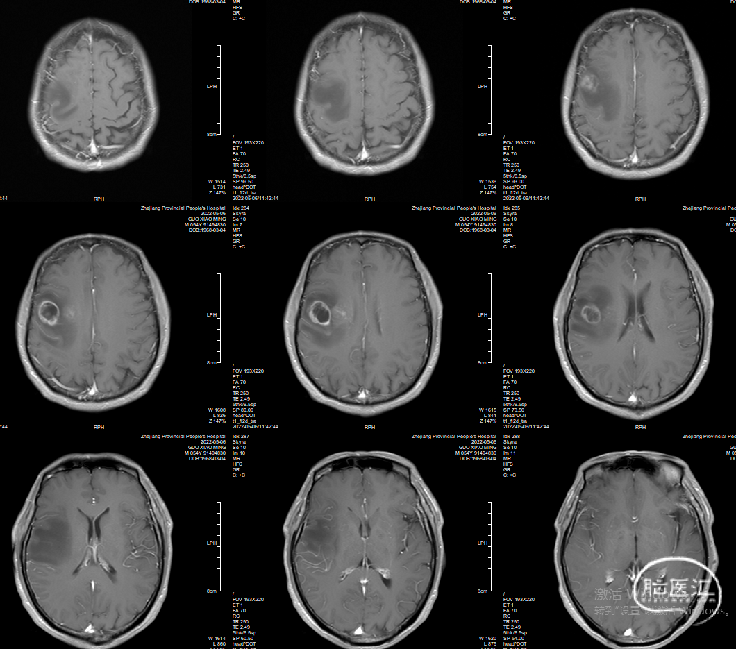

术前MRI: